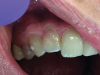

(5.) Close-up clinical and radiographic views of an ECR lesion presenting as a pink spot on the cervical aspect of tooth No. 7.

Figure 5

(6.) Close-up clinical and radiographic views of an ECR lesion presenting as a pink spot on the cervical aspect of tooth No. 7.

Figure 6

Early-stage ECR lesions may not be readily detected on clinical examination. Because the portal of entry normally occurs cervically, ECR lesions are often only palpable subgingivally. Cervical cavitation may be present and can be diagnosed by probing with an explorer-type instrument. When an explorer is used, ECR lesions will feel hard and scratchy like dentin with an irregular surface not like caries lesions, which feel sticky or soft.7,17 The appearance of knife-edge borders around such a cavitation can also help to differentiate ECR from root caries.18 Furthermore, a pink spot or banding may be present at the cervical aspect of the tooth overlying the resorption cavity; however, this finding occurs rarely and may also infrequently be associated with internal root resorption lesions (Figure 5 and Figure 6).19 The pink discoloration results because the granulation tissue of the resorptive defect has become visible through the overlying dental hard tissues. Generally, the gingiva adjacent to ECR lesions can be inflamed and may exhibit easy bleeding on probing due to its vascularity.1,7,14,19 Therefore, the presence of irregular, inflamed, and/or hyperemic gingiva may serve as early indicators of an ECR lesion. More advanced lesions may entrap debris within them, creating a secondary periodontal abscess or caries lesion with associated signs and symptoms.14,6